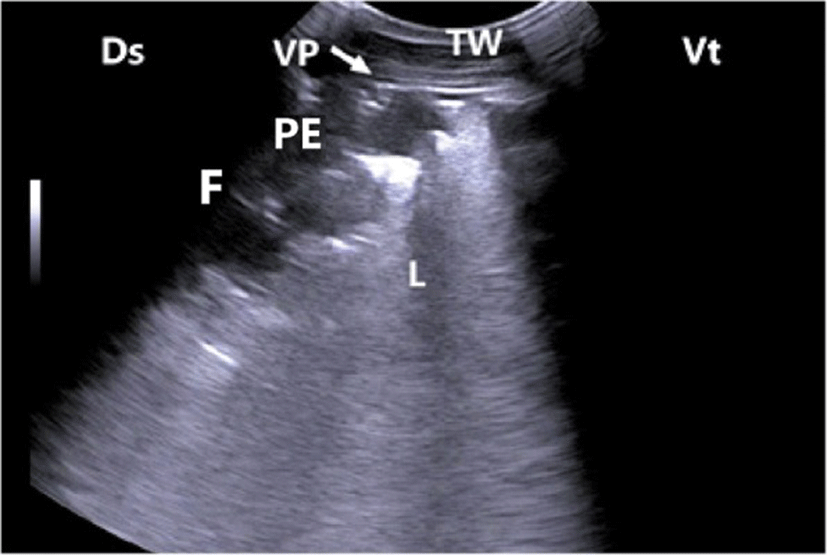

In calves with bronchopneumonia, the ultrasonographic appearance of diseased lungs varied depending on the degree and type of lesions. Four cases showed small hypoechoic circular zones (about 7 mm in diameter) at the lung surface, representing a superficial fluid alveologram with a comet-tail artifact (Fig. 5a). The ultrasonographic features of the lung tissue in ten calves with bronchopneumonia appeared hypoechoic and its echo texture may look like liver parenchyma, representing pulmonary consolidation and containing ramified fluid bronchgrams (Fig. 5b). These consolidated areas have a homogenous and echoic basic texture with well defined borders. Lesions of lung consolidation were found on the left side of the thorax in 7 cases and on the right side of the thorax in 3 cases. In three cases, air-filled alveoli were imaged in this hepatized lung tissue, appearing as hyperechoic spots in the consolidated parenchyma. Occasionally, hyperechoic reflective bands of an air-filled bronchus were detected in the pulmonary tissue, representing air bronchoaerograms. The most affected lobes were the cranial (8 calves) (Fig. 5c), then the cardiac (2 calves) and intermediate (2 calves) lobes. Thoracic ultrasonographic examination of calves with pleurisy revealed presence of thick fragmented visceral pleura and filling of pleural sac with echogenic fibrin shreds and anechoic exudates (Fig. 6). Moderate pleural effusion was seen in 3 cases, while pleural irregularity was observed in 4 of 8 cattle calves with pleurisy. One case showed roughened texture of the pleural surface causing narrow streaks of comet tails.

Ultrasonographic examinations of cattle calves with bronchopneumonia revealed presence of pulmonary consolidations, where the lung tissues appeared hypoechoic and their echo texture may look like liver parenchyma containing bronchoaerograms and/or brochograms in this region. As reported elsewhere [19], bronchoaerograms are small bronchi filled with air, which makes them appear hyperechoic, while bornchograms are anechoic tubular structures, representing fluid filled bronchi. In the current study, bronchograms resembled the blood vessels in the echogenicity. Therefore, Doppler ultrasonography was used to distinguish between blood vessels and bronchograms. Bronchograms appeared lacking the blood flow. Thoracic ultrasonography of calves with pleurisy showed varied images ranged from thickening and irregularity to fragmentation with pleural effusion of pleurae, indicating the degree and severity of illness. As mentioned before [24], ultrasonography allows evaluation of pleura and permits pleural effusion to be visualized and quantifies the nature and extent of the effusion.